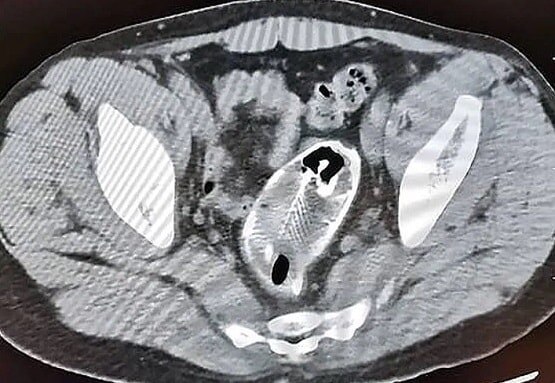

रिपोर्ट के मुताबिक डॉक्टरों ने बताया कि प्रभावित हिस्सा 19 सेन्टीमीटर लंबा, 18 सेन्टीमीटर चौड़ा और 12 सेन्टीमीटर गहरा था. इस समस्या के साथ ही मवाद के कारण लीवर की दीवारों पर छोटे-छोटे ट्यूमर उभरने लगे थे.

अंत में डॉक्टरों ने ऑपरेशन के जरिए युवक के लीवर में भरा हुआ मवाद निकाला. कुछ समय बाद दोबारा स्कैन करने पर सूजन और ट्यूमर की शिकायत बनी रही तो युवक के लीवर को काटने का फैसला किया गया. शख्स के लीवर के डेड टिशूज में अनगिनत छोटे-छोटे अंडे पाए गए थे.